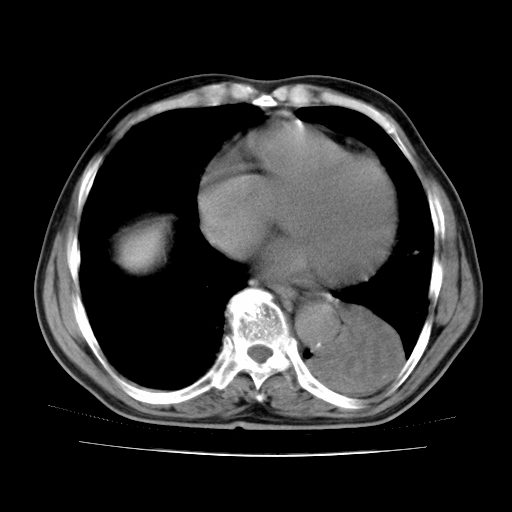

男,71岁,咳嗽,气喘10年,再发并咯血.胸片见气胸

考虑  左肺中心型肺癌伴阻塞性肺炎,肺不张,纵膈淋巴结肿大。慢支炎,肺气肿,左侧气胸肺压缩5%

1)考虑左肺中心型肺癌伴阻塞性肺炎、左肺下叶肺不张、左侧肺气肿,纵膈淋巴结转移。2)左侧气胸(肺组织压缩约5%)。

1)考虑左肺中心型肺癌伴阻塞性肺炎、左肺下叶肺不张、左侧肺气肿,纵膈淋巴结转移。2)左侧气胸。